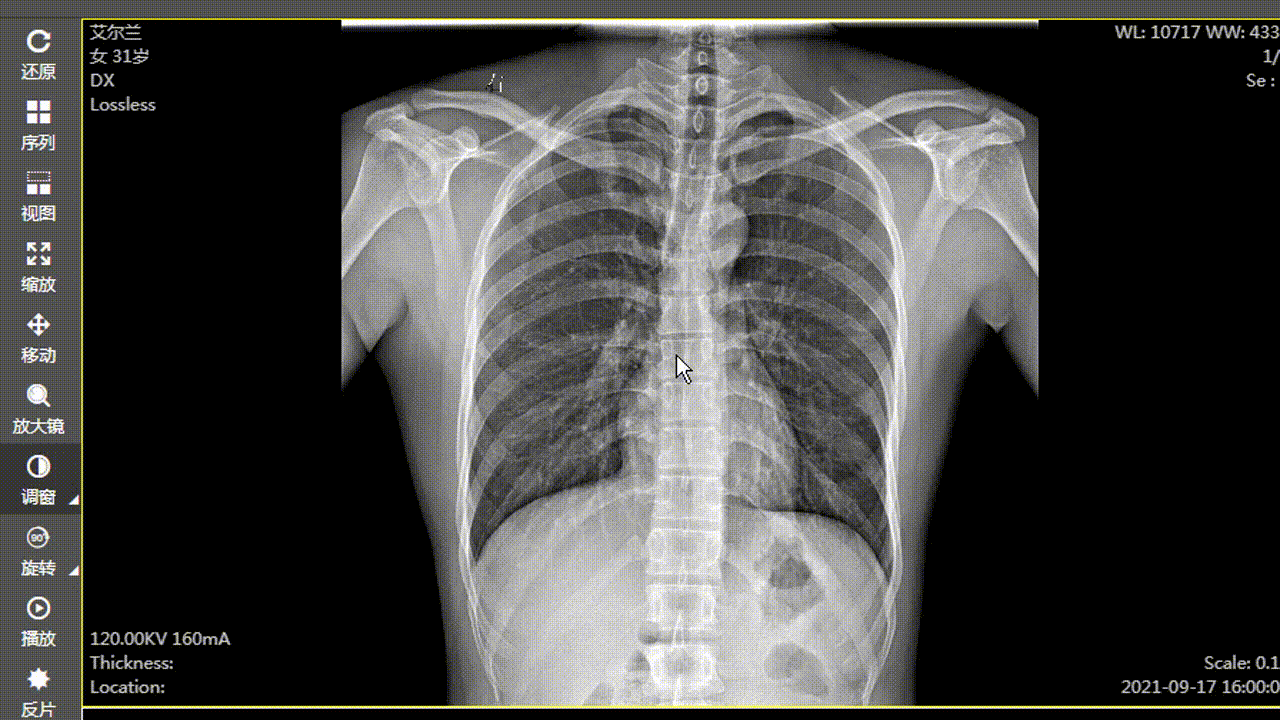

​ 在 web 版阅片器(图像显示工具)的开发工程中发现,在对 dr、dx 这种大图(图像普遍是 2000px 左右宽高的图像,每个像素大小是 16 位或者 32 位的)进行调窗时,浏览器直接卡死,图像显示变化有很大延迟。后来查阅资料,使用 gpujs 来实现调窗时图像的处理,结果:调窗时图像显示变化变得比较线性,性能估计提升 5/6 倍,能满足业务需求。当然,图像的一些高级处理,都是可以用 gpujs 来实现,调窗只是一个点。

​ 使用前效果: